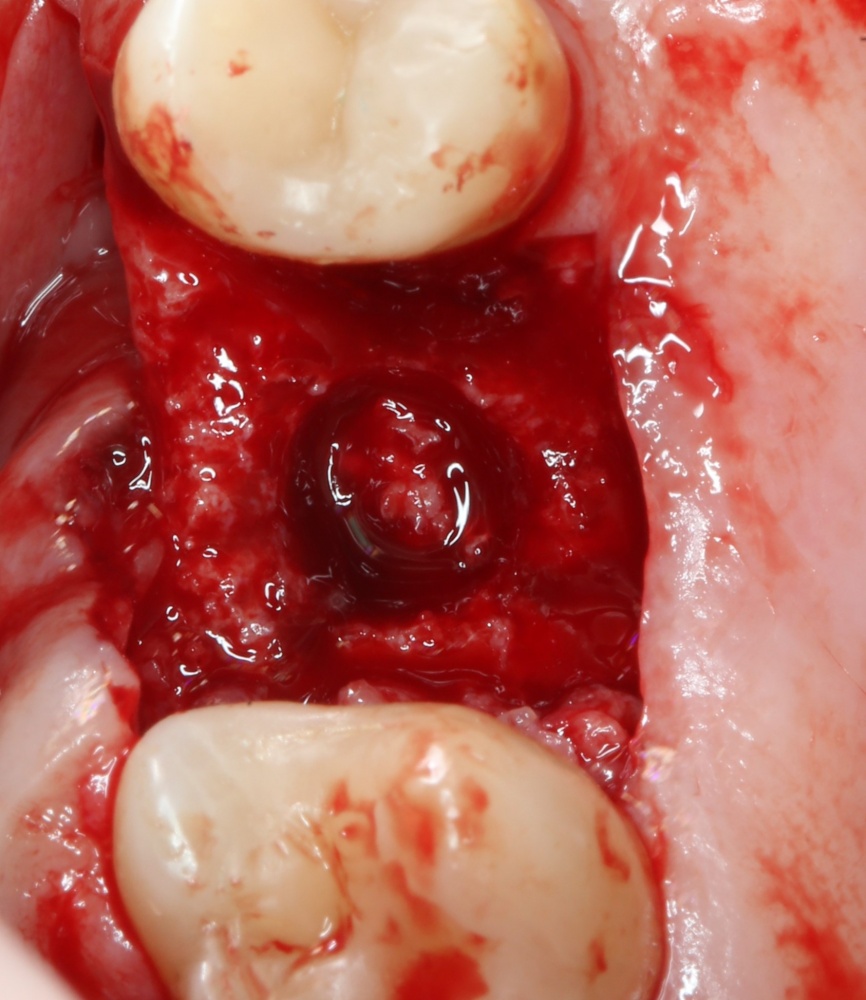

Кстати, обрати внимание на ширину альвеолярного гребня (левая картинка). Она чуть меньше 3 мм. Это объясняет, почему я засомневался в возможности установки имплантатов одновременно с остеопластикой. Понятно и без КЛКТ.

Возвращаемся к основной операционной области. Еще раз посмотрим на альвеолярный гребень, поофигеваем от его ширины и моих грандиозных планов:

На этом месте мне следует дать некоторые пояснения.